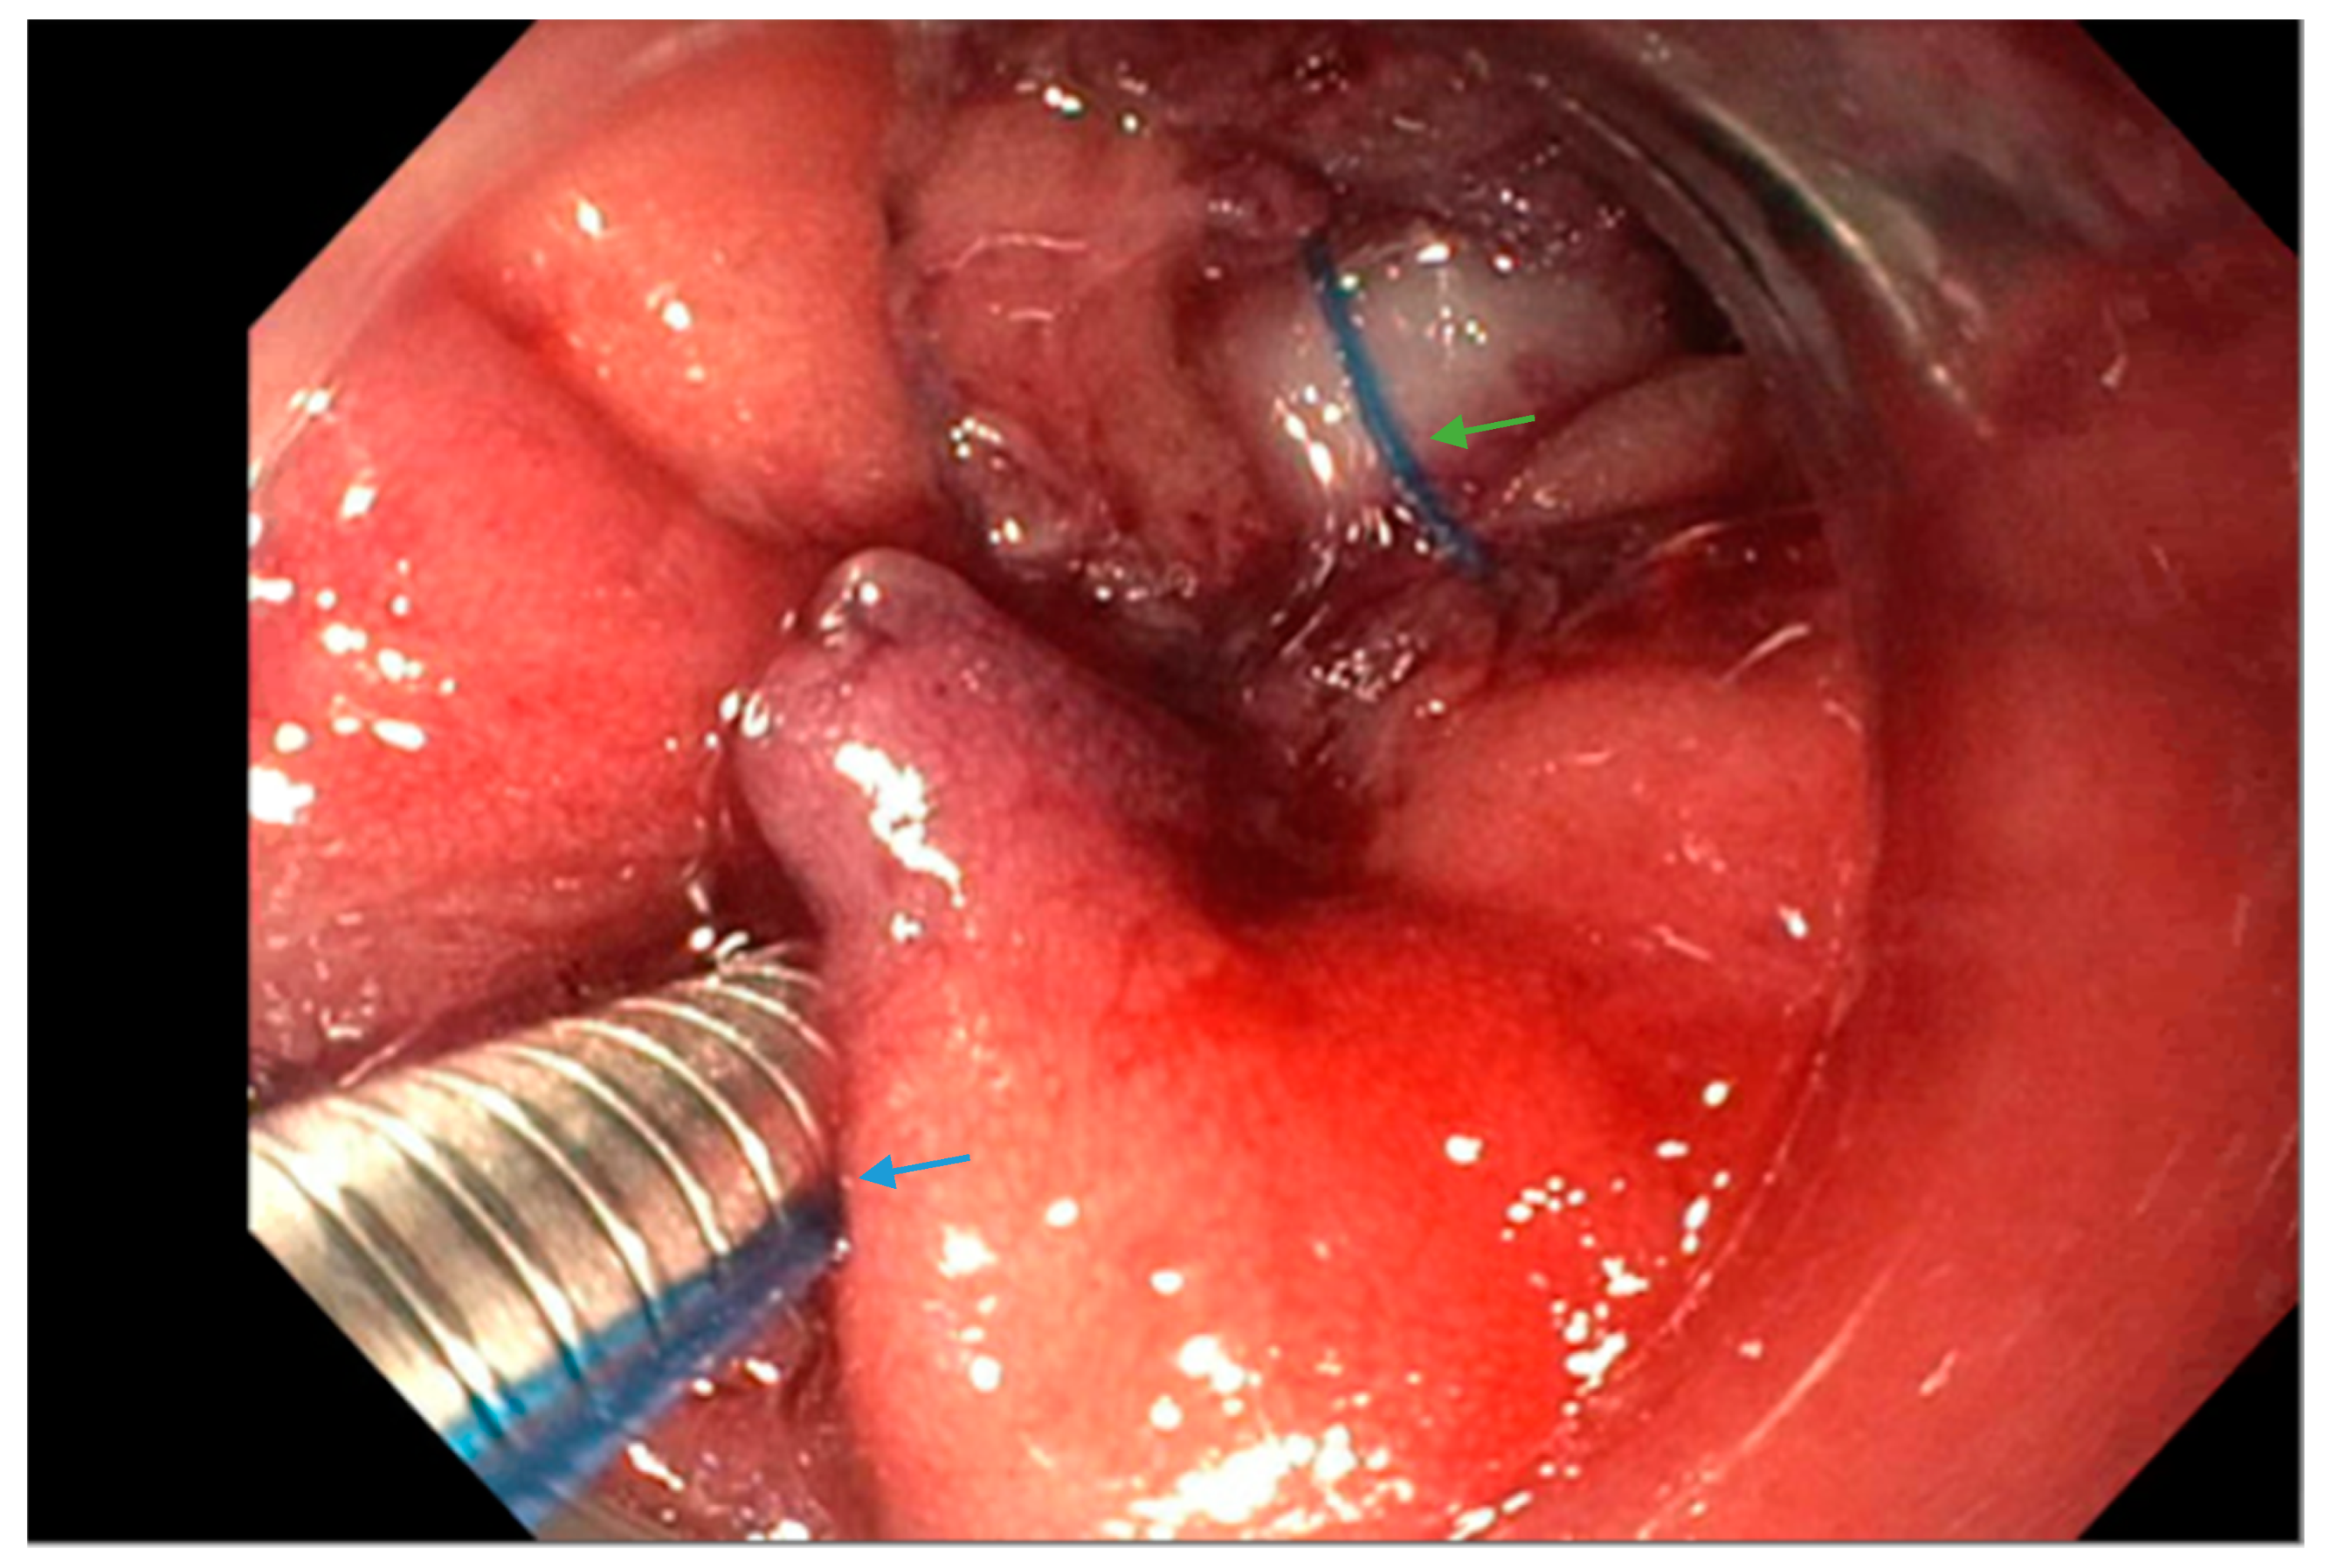

3.4. Over-the-Scope Clips

3.5. Endoscopic Suturing